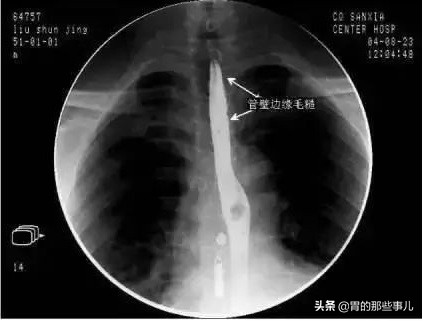

胃食管反流引起胸痛的主要原因,在于食管由会厌部起始经过胸腔,在贲门口处与胃相连,当食管壁受到刺激时,就可引起胸痛。胃食管反流由于胃酸、胆酸和胰酶等化学物质刺激食管下段的化学感受器,以及不断反流引起的食管炎和溃疡等,都会刺激食管产生明显的胸痛。所以刚开始一个简单的“反酸烧心”伴随患者大半生被认为是个“简单”病,而挥之不去。不断折磨他数年则是个“治不好”的怪病。最终疾病发展到引起食管剧烈疼痛。所以当该病仅表现为“反酸、胃灼热”时就应该引起足够的重视,循序渐进的从生活调理药物治疗乃至必要时抗反流手术治疗,而不至于长期在很低的生活质量下生活,甚至危及生命。